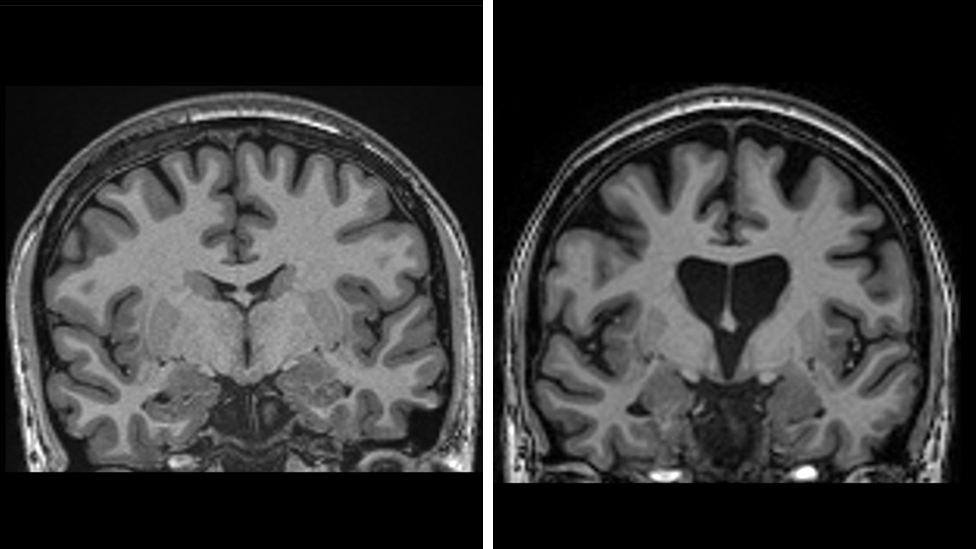

The data also indicates that the treatment is preserving brain cells. Neurofilament levels in spinal fluid—a clear indicator of brain cell death—were expected to rise by a third if the disease kept advancing, but instead were lower than the initial levels of the trial.